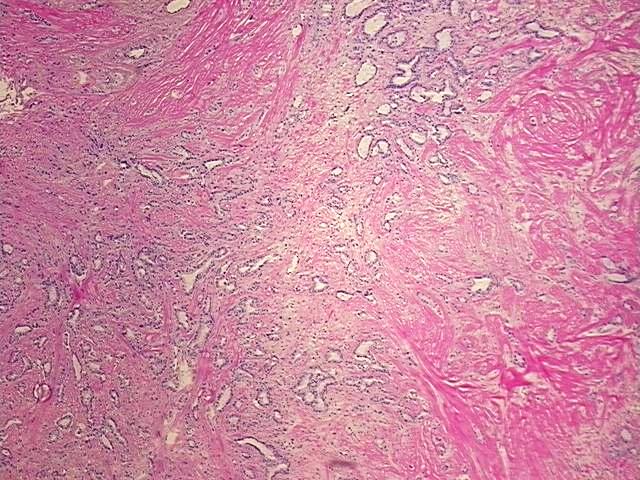

4x Image